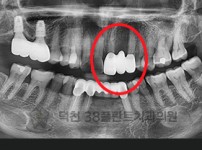

치료전후